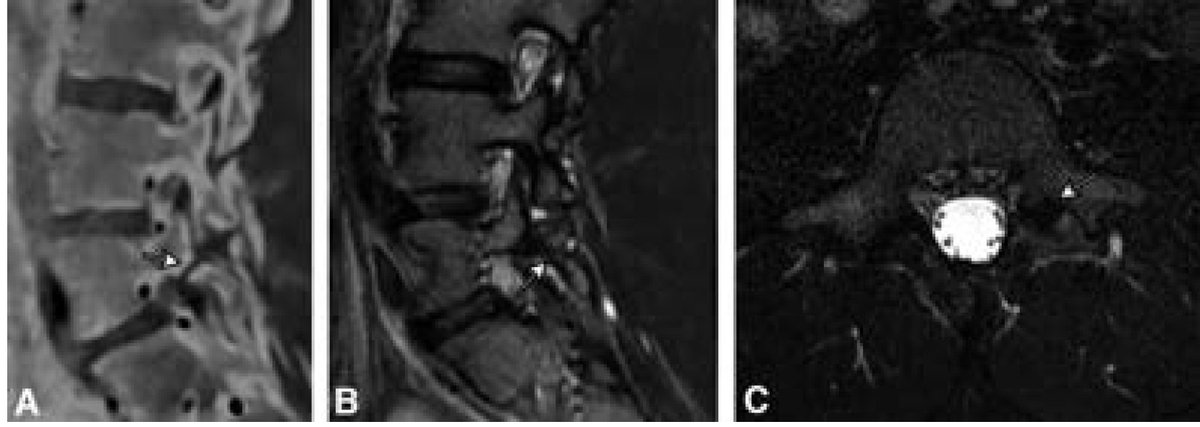

ASSR COTW History: Headaches & Vision Changes Case c/o Alexis Salsbury from UPMC Radiology #SpineRad #NeuroRad #MedEd #FOAMed #FOAMrad #neuroradiology #radiology

ASSR COTW History: Spontaneous intracranial hypotension (SIH) refractory to nontargeted epidural blood patches Case c/o Tim Amrhein, MD from Duke Radiology #SpineRad #NeuroRad #MedEd #FOAMed #FOAMrad #neuroradiology #radiology